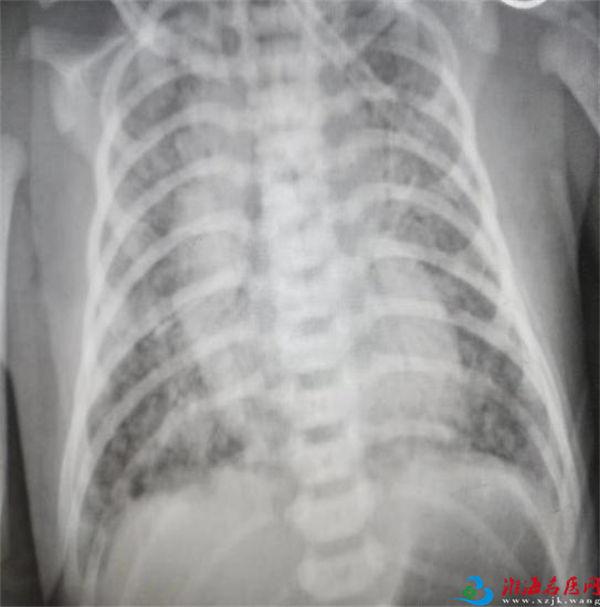

患儿被迅速转运至NICU后,董雪萍和团队医护人员立即进行了一系列紧急检查。通过X光胸片,医生们清晰地看到患儿肺部有大片阴影,结合临床表现和血气分析结果,确诊患儿为新生儿胎粪吸入综合征伴肺出血。